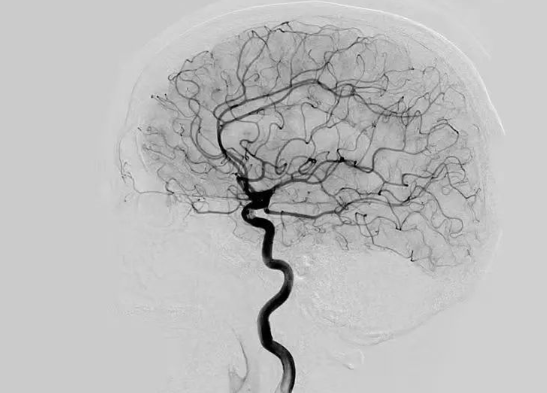

腦血管造影是什么檢查項(xiàng)目

在腦血管疾病篩查與診療中,腦血管造影是高頻提及的檢查方式,不少患者拿到檢查建議時(shí),都會疑惑“腦血管造影是什么檢查項(xiàng)目”。作為診斷腦血管